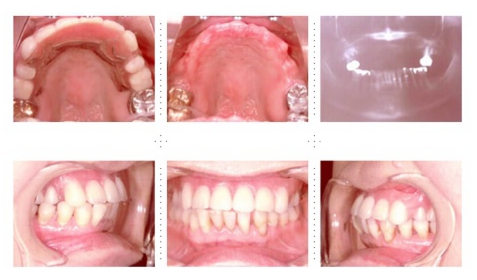

症例4

57才 女性

知人の歯科医からのご紹介。良く噛めない為、元気が出ない。介護の仕事を続けるためにも、歯を治療して自分がもっと元気になりたい。最初は部分的に治療する予定だったのですが、歯のない部分はインプラントを埋入し、最終的には上下顎全ての歯を治療し、しっかりものが噛めるようになりました。